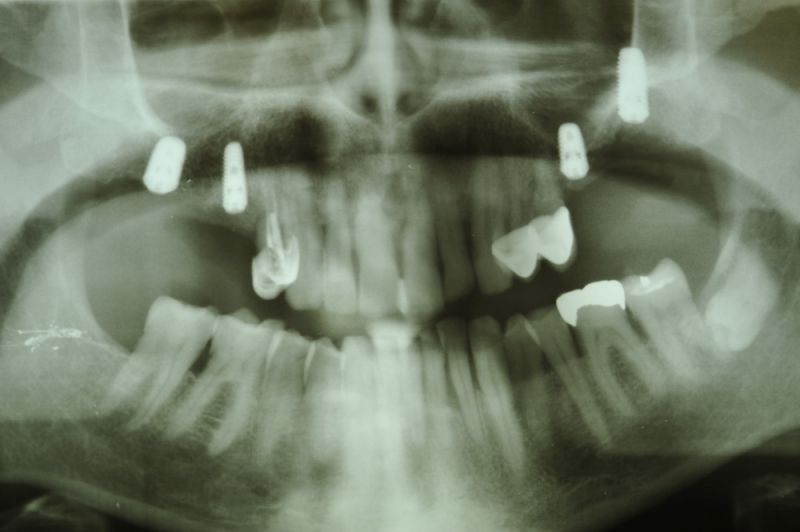

73 jähriger CMD-Patient im Recall

Der Patient hat vor 5 Jahren eine äußerst umfangreiche und komplexe CMD-Behandlung abgesclossen und befindet sich seitdem in einem engmaschigen vierteljährlichen Recall!

Seit 5 Jahren ist der Zustand des Patienten vollkommen unverändert!

Die aktuellen Taschentiefen liegen bei 2 Millimeter! Auch im Bereich der Implantate!

Das Allerwichtigste bleibt aber der engmaschige, vierteljähliche Recall, der aus mehr besteht, als nur einem Zahnsteinentfernen! Wichtig ist die fortlaufende Dokumentation der verschiedenen Parameter der parodontalen Gesundheit und genauso wichtig eine Röntgenkontrolle etwas alle ein bis eineinhalb Jahre.